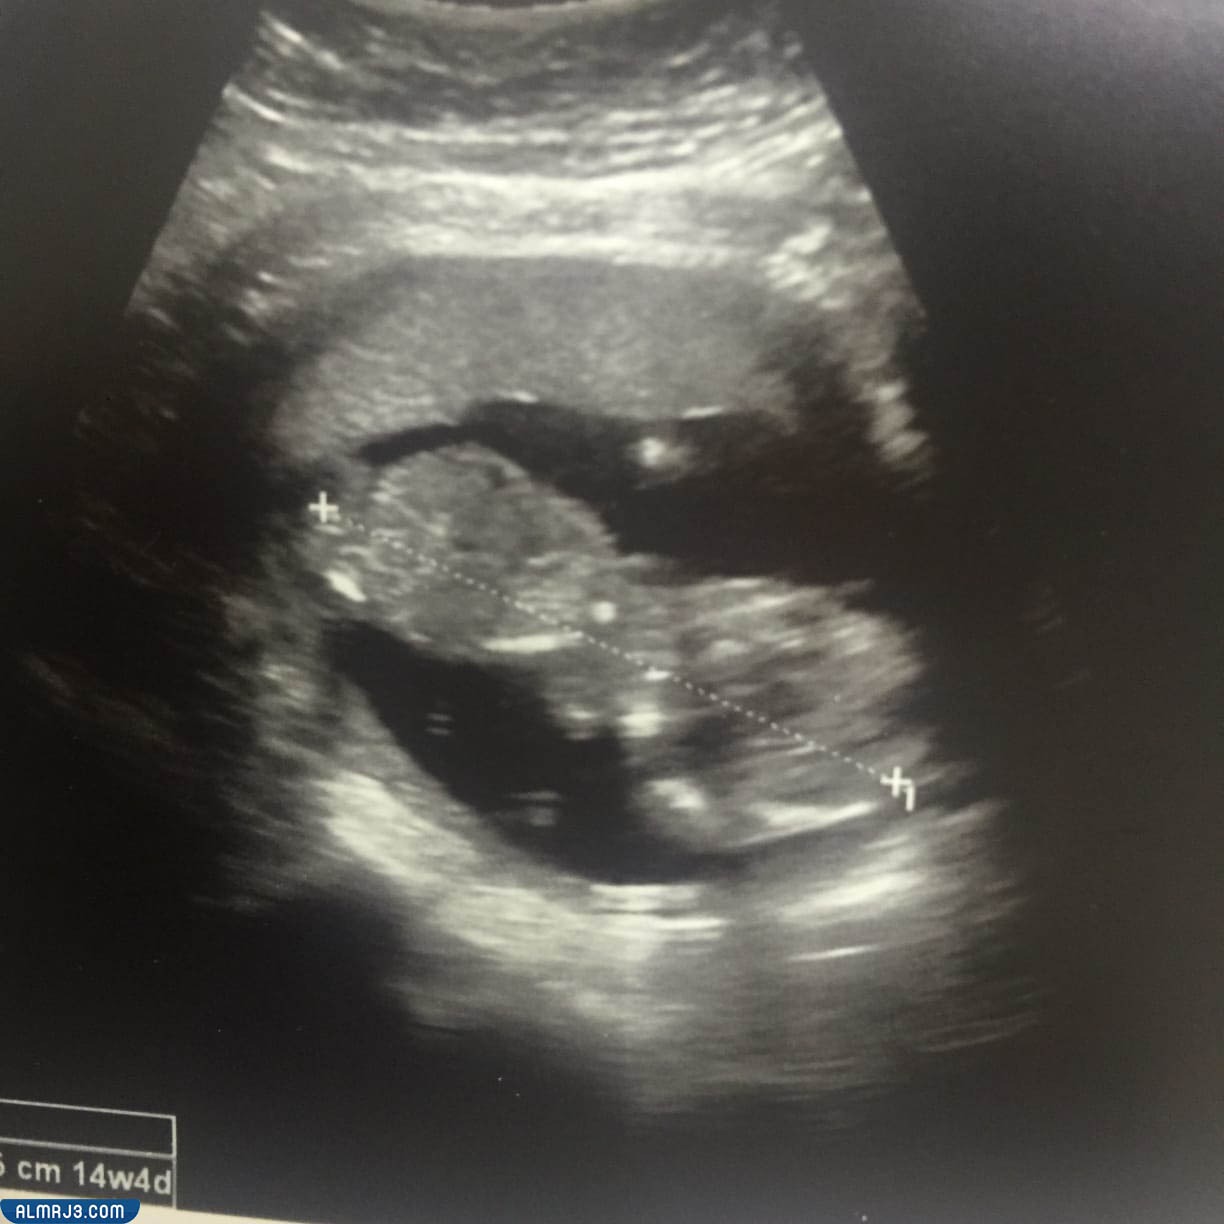

شكل الجنين الأنثى في الشهر الثالث بالسونار

وفي هذا الشهر من الحمل تكون الأم مازالت تعاني من أعراض الحمل المختلفة، ولكنها في نفس الوقت ترغب في تحديد نوع الجنين الموجود داخل الرحم، ففي حال كانت الجنين أنثى، فتكون الحديبة التناسلية الخاصة بها تأخذ زاوية تقل عن 30 درجة، وذلك لتكون بالتقارب أو التوازي مع العمود الفقري،

شكل الجنين البنت في الشهر الرابع بالسونار

وفي الشهر الرابع من الحمل يمر الجنين بالعديد من التغيرات، والتي يستطيع الطبيب ملاحظتها داخل أجهزة السونار بمنتهى السهولة، وذلك مع تكون كل من الجلد والأعضاء التناسلية، فستكون لدى الجنين البنت شفرتان، وذلك إلى جانب العضو التناسلي الخاص بها، والذي يمكن رؤيته بسهولة في حال كانت تأخذ الجنين البنت وضعية مناسبة لذلك الأمر.